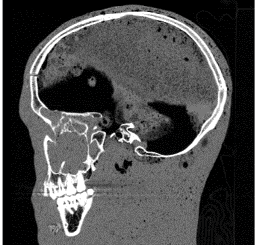

CT-Scanning – Kadlec Medical Center, Richland, WA

These CT slices are of the Case 0102 phantom cranium. Views were selected form the transverse, coronal, and sagital planes.